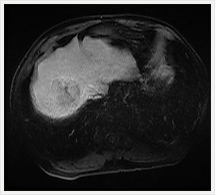

肝臓ダイナミック撮影

当院では、肝腫瘍を疑った場合MRI検査用のEOB・プリモビスト造影剤を使用して検査しています。造影剤を急速静注しながら連続撮影するダイナミック撮像では、造影剤注入30秒後に血流の豊富な部位(腫瘍など)を撮影する動脈相、3分後に造影剤は肝臓の正常な部位に分布し、最初に造影された血流の豊富な部位での造影剤の濃度が下がる平衡相を撮影しています。

EOB・プリモビストは正常な肝細胞に取り込まれ、転移性肝癌やほとんどの肝細胞癌など肝細胞機能を持たない組織には取り込まれない特徴があります。そのため、15分後に撮影すると、正常な機能を持った肝細胞だけが強く造影され、肝細胞機能を持たない異常な組織をより明確に見分けることができます。